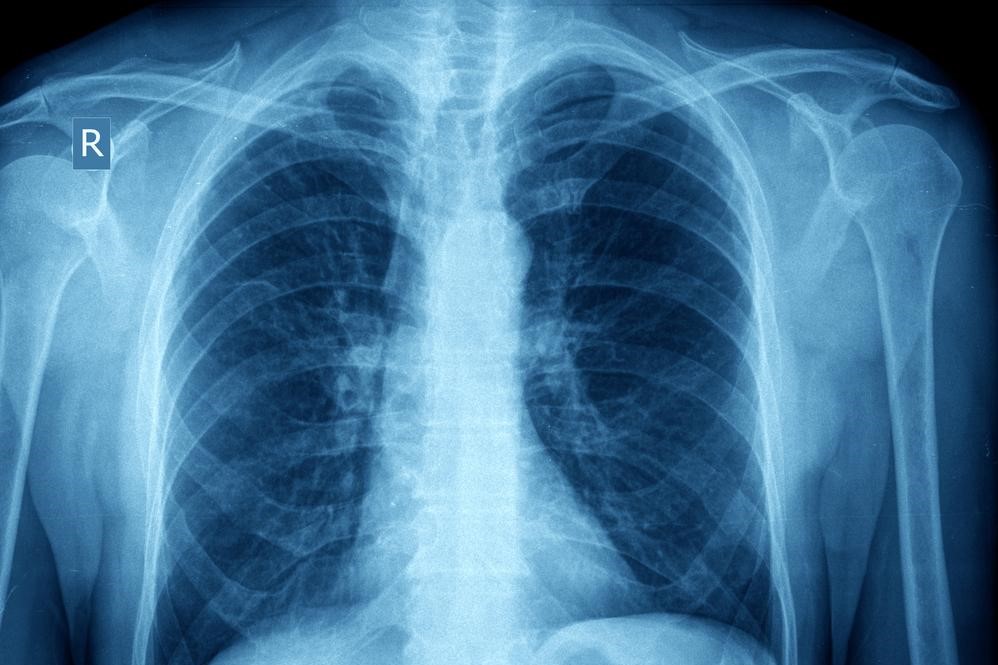

Bronchial asthma is a chronic respiratory disorder that affects millions of people across the world, leading to varying degrees of breathing difficulty — from mild episodes to severe, potentially life-threatening attacks. The condition arises when the airways inside the lungs become inflamed, narrow, and filled with excess mucus, restricting airflow and making it difficult to breathe. Gaining a clear understanding of this condition, recognizing its symptoms, and learning how to manage it effectively can make a profound difference in maintaining lung health and improving day-to-day quality of life.

Asthma is characterized by long-term inflammation of the airways that leads to recurring episodes of wheezing, shortness of breath, chest tightness, and persistent coughing.

During an asthma flare-up, the muscles surrounding the airways constrict, the lining of the bronchial tubes becomes swollen, and thick mucus accumulates — all of which make breathing more laborious. These attacks can occur unexpectedly and may be triggered by a wide range of factors, causing significant anxiety and distress.